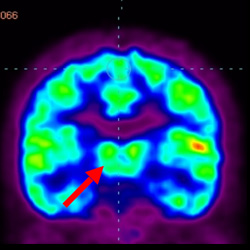

細胞治療前 PET CT 掃描顯示神經組織中的藍/黑色區域,表明腦癱引起的大腦損傷。

細胞治療后,藍色和黑色區域減少,并且看到更活躍的區域。這表明損傷減少并改善了大腦功能。

這證明細胞療法是治療腦癱兒童安全有效的方法。細胞療法可以更新大腦損傷的核心,并且可以通過 PET CT 掃描來監測大腦的改善情況。這些細胞療法與標準治療一起促進腦癱兒童的生長和改善。